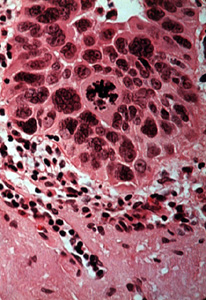

Una vista a más aumentos muestra  las anormalidades celulares similares a aquéllas descriptas en el displasia de la mucosa, dilatación vascular y degeneración del colágeno extensa ("elastosis senil"). Éstas son las alteraciones debido a la radiación solar.

Se muestran inflamación crónica, "elastosis senil" y displasia del epitelio con oscuridad anormal agrandada de los núcleos más mitosis, con este poder de resolución, en la queilítis actínica.